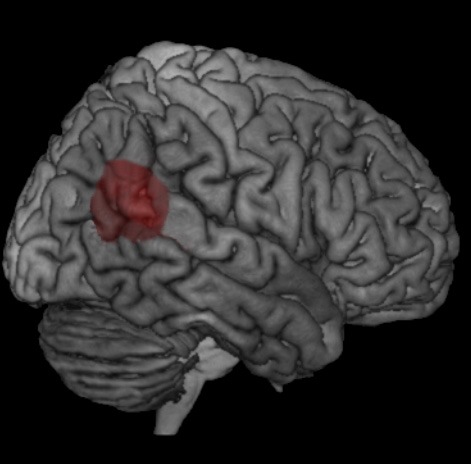

La décorporation est liée à des lésions au niveau de la région du cerveau située entre le lobe temporal et le lobe pariétal, appelée jonction temporo-pariétale (cf. les illustrations ci-jointes). Dans cette région du cerveau, différents signaux corporels sont traités, tels que le sens du toucher, de l'équilibre ou de la vue. Ces signaux nous aident à localiser notre corps dans l'espace. Les chercheurs avancent deux causes possibles pour les décorporations: d'une part, la lésion au niveau de la jonction temporo-pariétale empêche de ressentir le corps comme une unité cohérente, et de l'autre, la perception spatiale est modifiée par des signaux contradictoires du sens de l'équilibre. Lorsque ces deux dysfonctionnements coïncident, les personnes concernées ont l'impression de quitter leur corps.